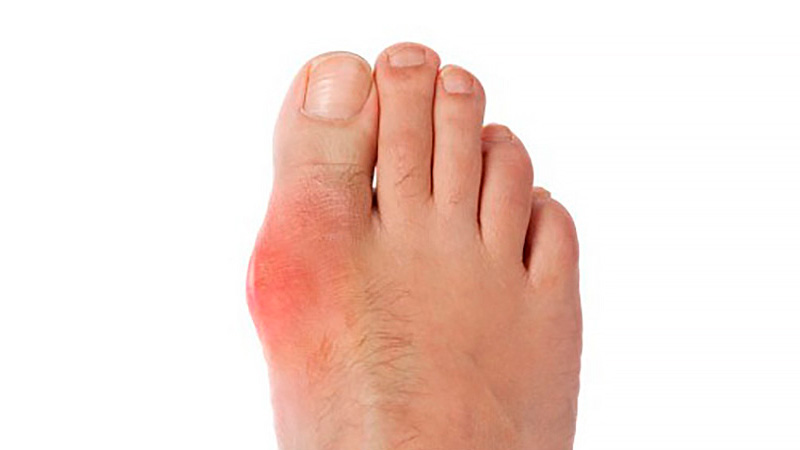

En pacientes con gota y sin enfermedad coronaria, el uso prolongado de alopurinol protege contra el primer síndrome coronario agudo (SCA) en comparación con los no usuarios. Por el contrario, los iniciadores del alopurinol, que posiblemente tenían más inflamación sistémica, tenían un mayor riesgo de SCA por primera vez en comparación con los usuarios a largo plazo. BMJ Open, 27 de febrero de 2025

Seguridad de la profilaxis con colchicina o con antiinflamatorios no esteroides al iniciar el tratamiento reductor de uratos para la gota

En este estudio observacional se comparó el inicio de alopurinol para la gota acompañado de profilaxis con colchicina o con AINE versus alopurinol sin profilaxis asociada. Los eventos adversos fueron más comunes cuando se inició alopurinol con profilaxis, particularmente la aparición de diarrea con el uso de colchicina. Otros eventos fueron poco comunes, lo que brinda tranquilidad a los pacientes y a los médicos para permitir la toma de decisiones compartida. Annals of the Rheumatic Diseases, octubre de 2023.